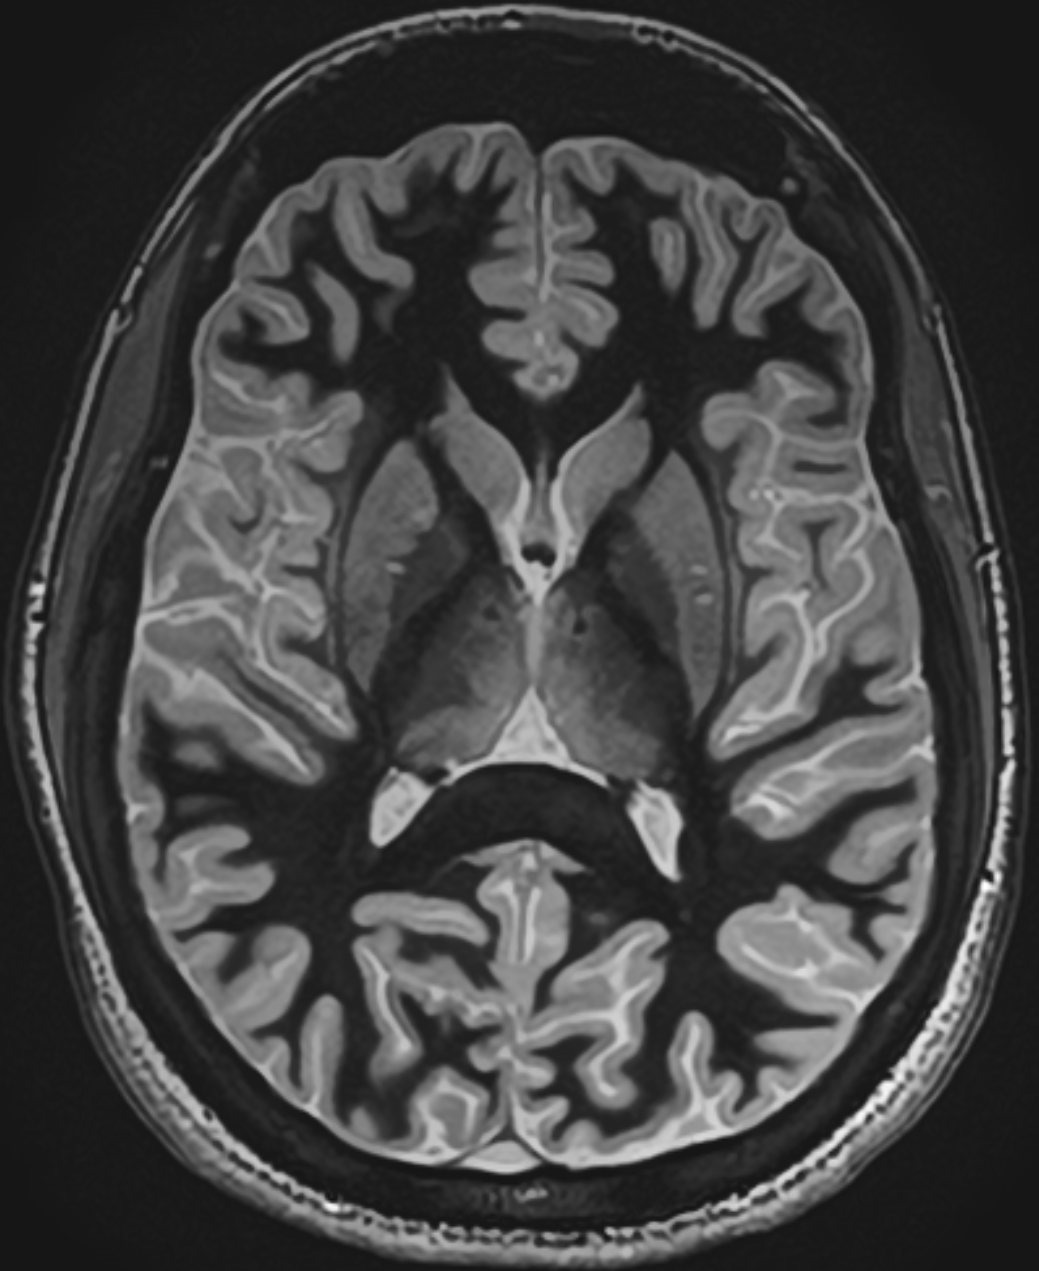

Located at the geometric center of the brain, the thalamus sits at the crossroads of nearly every major neural circuit — a convergence point for sensory, motor, limbic, and cognitive pathways.

MRI brain full

White-Matter-Nulled MPRAGE